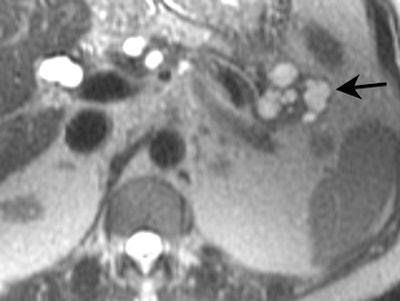

![]() |

| Mucinous cystadenocarcinoma. Presence of mural calcifications (arrow) and septations are suggestive of malignancy. |